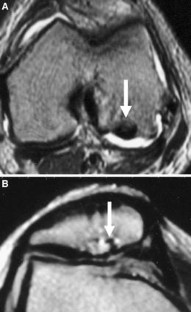

Fig. 2